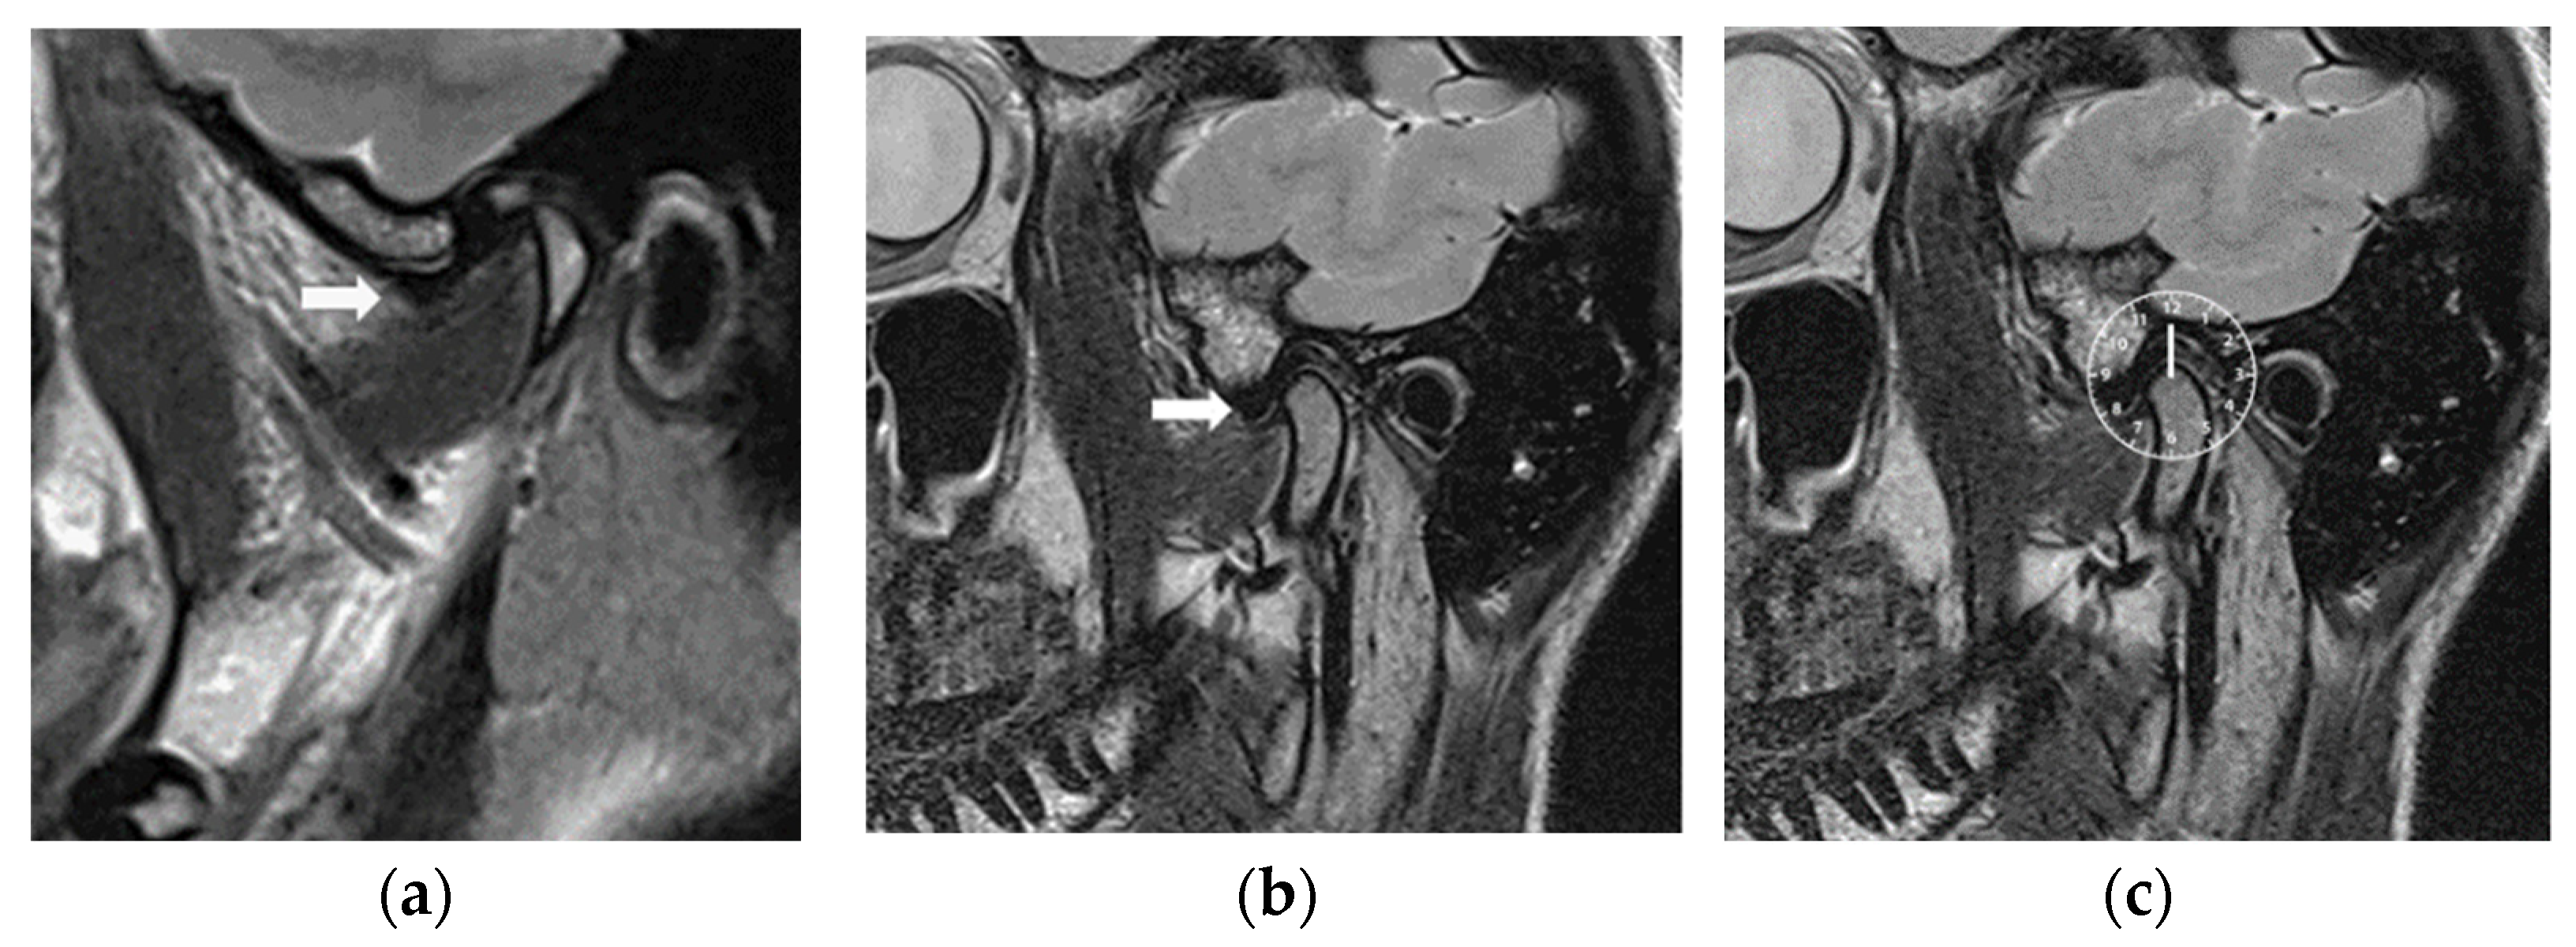

2.2.3. Magnetic Resonance Imaging